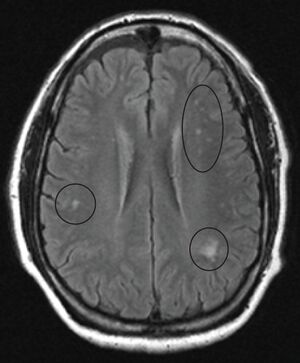

MRI image of the brain in vitamin B

12 deficiency, axial view showing the "precontrast FLAIR image": note the abnormal lesions (circled) in the periventricular area suggesting white matter pathology.

In the brain itself, changes are less severe: They occur as small sources of nervous fibers decay and accumulation of astrocytes, usually subcortically located, and also round hemorrhages with a torus of glial cells.

MRI of the brain may show periventricular white matter abnormalities. MRI of the spinal cord may show linear hyperintensity in the posterior portion of the cervical tract of the spinal cord, with selective involvement of the posterior columns.